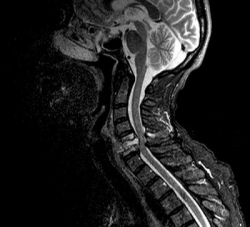

Двигательные нарушения, возникающие на спинальном! уровне, при поражении задних столбов, описаны во всех классических руководствах в разделе сенситивных (заднее столбовых) атаксий, однако в последнее время имеются работы, в которых данные нарушения рассматриваются и обсуждаются рядом авторов с точки зрения синдрома афферентного пареза, тем самым указывая на необходимость более широкого подбора новых методик в реабилитационной терапии.

Формирование подкорковых афферентных парезов, на наш взгляд, происходит по двум причинам: с одной стороны, имеет место нарушение корково-подкорковых взаимоотношений,, т. е. вертикальная тензорная дезинтеграция, с другой -страдает бензомоторное взаимодействие между зрительным бугром и моторными подкорковыми узлами; в результате выпадает подкорковая память на движение и выбывает афферентная основа организации синергии.